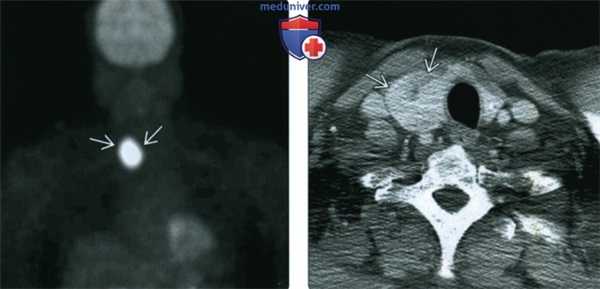

(Слева) ПЭТ в прямой проекции. Участок интенсивного захвата ФДГ в нижней части шеи справа у пациента с кожной Т-клеточной лимфомой. Исследование выполнялось для того, чтобы уточнить локализацию метастазов.

(Справа) КТ с КУ, аксиальная проекция, срез через нижнюю часть шеи. В правой доле щитовидной железы имеется крупный неоднородный узел. Признаки прорастания за пределы железы отсутствуют. Шейная лимфаденопатия отсутствует. Повышенный захват ФДГ может быть характерен и для доброкачественных, и для злокачественных новообразований щитовидной железы. Тонкоигольная биопсия обычно выполняется для исключения злокачественного процесса.